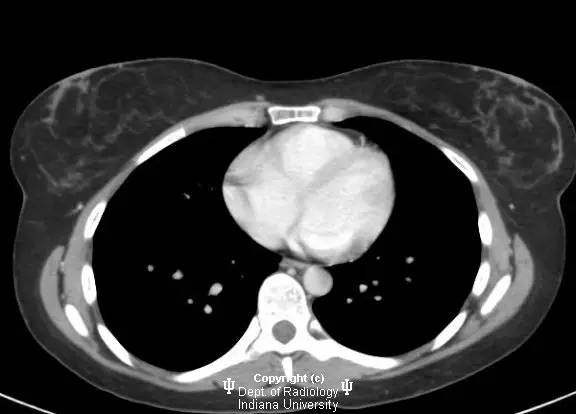

【影像学表现】

乳腺钼靶左乳腺内上象限见3.1cm卵圆形等密度肿块,部分界限清晰。超声见一2.5 x 2.1 x 1.9 cm混合回声肿块,宽大于高,边界清晰,后部回声增强。

浸润性导管癌

Invasive ductalcarcinoma

浸润性导管癌为乳腺癌的最常见类型(80%),有人认为由导管原位癌进展而来,病变可沿着真皮淋巴管播撒而导致皮肤增厚和乳头内陷。肿瘤多无症状,筛查时发现。女性多于中年好发。浸润性导管癌也是男性乳腺癌的最常见类型。淋巴结累及时提示预后不良。诊断多经超声引导下或立体定位活检。局限性病变治疗主要为手术,也可行放疗,化疗和激素治疗。